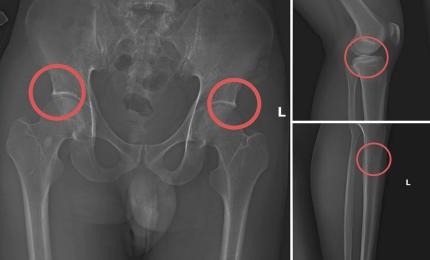

Cách cán bộ y tế dùng búa đinh đục gãy xương chân để trục lợi bảo hiểm

Ngày 28/11, Công an tỉnh Phú Thọ cho biết Cơ quan Cảnh sát điều tra đã khởi tố, tạm giam Tạ Minh Châu, 29 tuổi, nguyê